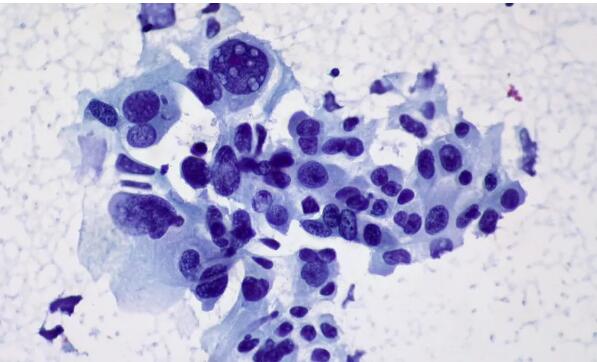

之前的大量研究表明,肿瘤里面的浸润T细胞(TILs)是有高度的异质性的[2-4]。Newell团队也发现,肺癌和肠癌患者的肿瘤浸润性杀伤性T细胞也存在高度的异质性。

他们使用质谱流式细胞术联合主要组织相容性复合体(MHC)四聚体染色技术,分析肿瘤中T细胞对1091个假定的新抗原,123个肿瘤相关抗原和46个与肿瘤无关的抗原(主要是病毒抗原)的特异性识别情况。

研究人员分析了它们表面的CD69和/或CD103,这两个蛋白都是肿瘤浸润T细胞的标志性特点[5],结果发现大量的细胞都表达了这两个标志物,这就表明这些肿瘤不相关的CD8+ T细胞应该是肿瘤自己的,不是经过血管从其他受感染的地方溜达过来的。

这个发现表明,并不是所有的CD8+ 肿瘤浸润T细胞都是特异性识别肿瘤表面的抗原的,有些旁观者CD8+ 肿瘤浸润T细胞特异性识别癌症不相关的抗原决定簇。(至于为什么会这样,作者没有探讨,隐约感觉背后有大秘密)